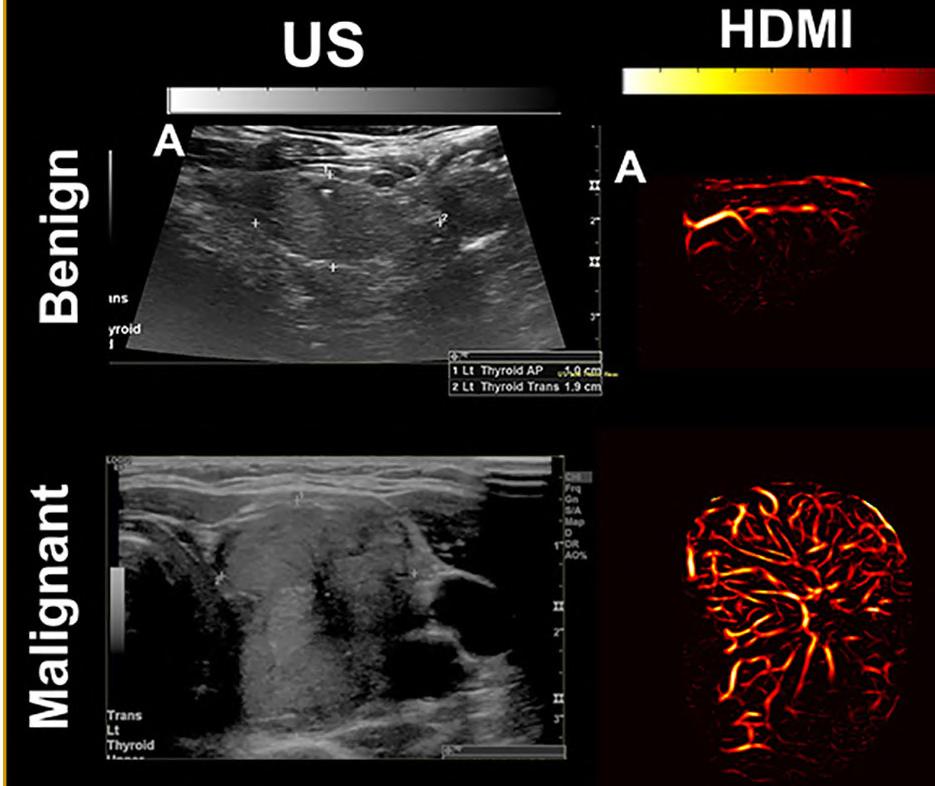

Known as high-definition microvasculature imaging (HDMI), the new technique noninvasively captures images of minute vessels within tumors and automatically categorizes the masses .

ach year, over 40,000 new thyroid cancer cases are reported. While 60-80% of patients with thyroid tumors undergo biopsies, the financial and potential physical toll of these procedures may be unnecessary for those with benign tumors. It is presently challenging for medical practitioners to accurately gauge the severity of a tumor, with different doctors having divergent opinions on a tumor’s threat level.

Standard ultrasound methods, which generate images of tissues and organs based on the sound waves they reflect, are efficient at identifying thyroid tumors. However, the technology can struggle to distinguish the minute sounds emitted from small blood vessels, or microvasculature, from those of the surrounding tissue, despite microvasculature providing vital clues about a mass’s cancerous nature. Although the introduction of contrast agents (chemicals easily visualized and commonly used in medical imaging procedures) allows ultrasound to display detailed images of tumor microvasculature, these substances need to be injected into patients and sometimes cause adverse side effects. While more recent ultrasound techniques can offer clearer nodule images, the ultimate evaluation still relies on the physicians’ subjective judgment.

Researchers at the Mayo Clinic College of Medicine and Science (Rochester, MN, USA; www.mayoclinic.org) have demonstrated that a pioneering cancer diagnostic method, which combines advanced ultrasound techniques with artificial intelligence (AI), can effectively diagnose thyroid cancer. This method — referred to as high-definition microvascu lature imaging, or HDMI — noninvasively captures images of the minute vessels within tumors and, based on vessel characteristics, automatically categorizes the masses. The researchers believe that HDMI could poten tially resolve the long-standing diagnostic challenge of assessing thyroid tumors in a clinical setting.

The researchers developed HDMI in an effort to develop an afford able, noninvasive imaging solution for evaluating thyroid tumors that could deliver quantifiable results and minimize errors. This system uses machine learning, a subset of AI, to assess high-resolution images of tumor microvasculature. The technique has already shown potential in accurately assessing breast tumors. In a recent study published in the journal Cancers, the team tested HDMI on thyroid tumors in 92 patients. They captured images of the tumors using HDMI and analyzed a dozen features related to the size and shape of the microvasculature in the images, including their density and branching points. All patients in the study, in consultation with their physicians, chose to have their tumors biopsied to confirm their malignancy status. Those with tumors deemed cancerous underwent surgery for the removal of the mass.

The researchers provided their machine learning algorithms with 70% of their imaging data from the patient tumors, along with the malignancy status, to teach algorithms how to interpret various features. Through a process of trial and error, the algorithms constructed predictive models, which were then used to determine the status of tumors imaged in the remaining 30% of the data. HDMI’s classifications were accurate 89% of the time, based on the clinical assessments of the biopsies and surgeries. These results suggest that HDMI could be a more reliable diagnostic method than traditional techniques and could spare numerous patients from unnecessary surgeries in the future. The researchers are now refining the method to enhance its accuracy even further. They plan to investigate its performance in diagnosing other types of cancer and whether it can assist in monitoring the effectiveness of chemotherapy on cancerous growths.

“Because HDMI allows you to objectively differentiate benign nodules from malignant ones, it could greatly improve diagnostic accuracy and reduce the number of unnecessary surgeries being done now,” said study author Azra Alizad, M.D., a professor of radiology and biomedical engineering at Mayo Clinic.

Image: A combination of advanced ultrasound and AI could upgrade cancer diagnostics (Photo courtesy of Mayo Clinic)